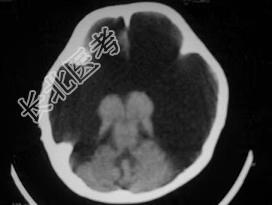

- 单项选择题女,1岁半, 头颅迅速增大,行CT检查如图, 请选出最可能的诊断  (    )

A、积水型无脑畸形

B、硬膜外血肿

C、硬膜下血肿

D、硬膜下积液

E、脑内血肿